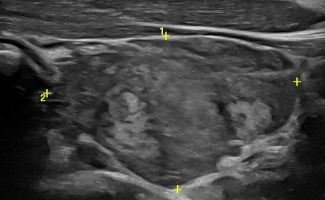

Υπερηχογράφημα Θυρεοειδούς και Ελαστογραφία

Το Υπερηχογράφημα Θυρεοειδούς Αδένα είναι σημαντικό διαγνωστικό εργαλείο για την αξιολόγηση και παρακολούθηση του θυρεοειδούς αδένα, καθιστώντας το ένα από τα πιο αξιόπιστα μέσα διάγνωσης πιθανών παθήσεων.

Με την τριπλή μελέτη του Θυρεοειδούς Αδένα, που περιλαμβάνει το B-Μode, το Έγχρωμο Υπερηχογράφημα και την Ελαστογραφία, γίνεται μια ολοκληρωμένη χαρτογράφηση του θυρεοειδούς αδένα. Το περίγραμμα, η αγγείωση και η ελαστικότητα του αδένα, καθώς και η υφή μίας πιθανής βλάβης αξιολογούνται με ακρίβεια και αξιοπιστία.

Πέραν των βασικών δομικών στοιχείων, το υπερηχογράφημα αποκαλύπτει πληροφορίες κρίσιμης σημασίας. Με αξιοσημείωτη ακρίβεια, ένας εξειδικευμένος Ιατρός- Ακτινολόγος ανιχνεύει και αξιολογεί:

• Διάχυτες νόσους (Θυρεοειδίτιδα Hashimoto)

• Εστιακές αλλοιώσεις (όζοι του θυρεοειδούς αδένα)

• Κακοήθεις βλάβες (καρκίνος θυρεοειδούς)